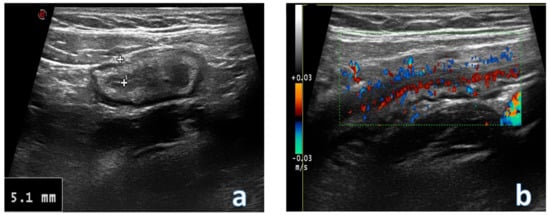

4. Acute Appendicitis